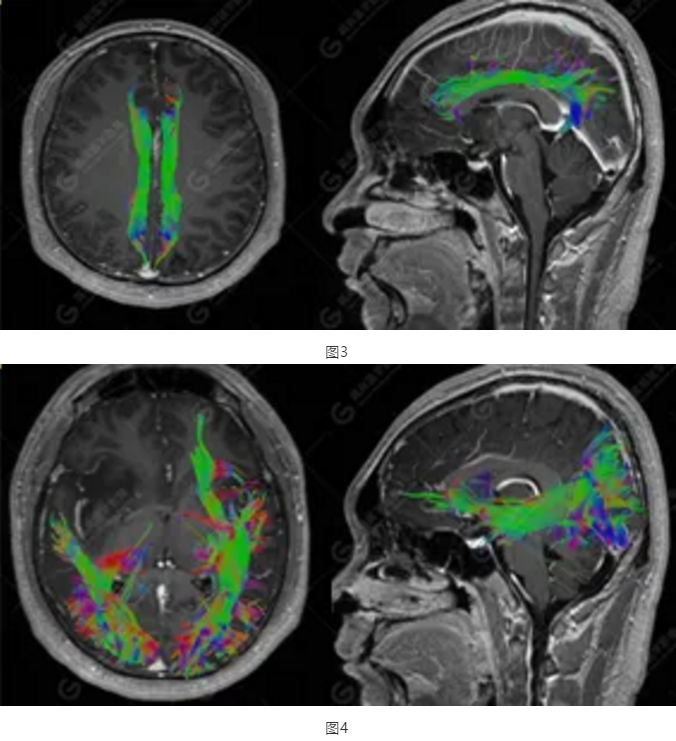

以上為DTI成像,圖1為皮質(zhì)脊髓束,圖2為胼胝體束,圖3為扣帶回束,圖4為額枕束。DTI成像示右側(cè)額枕束前部明顯受壓、部分未見顯示;胼胝體束、雙側(cè)扣帶束、皮質(zhì)脊髓束及左側(cè)額枕束形態(tài)可,纖維束未見明顯破壞,未見明顯稀疏減少。